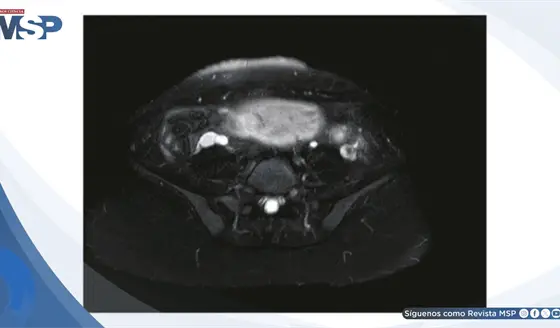

La ecografía abdominal mostró un apéndice aumentado de tamaño, no compresible, que medía 13,6 milímetros, con engrosamiento de su pared y presencia de estrías de grasa periapendicular, hallazgos altamente sugestivos de apendicitis aguda. Con base en estos resultados, el niño fue ingresado para intervención quirúrgica.